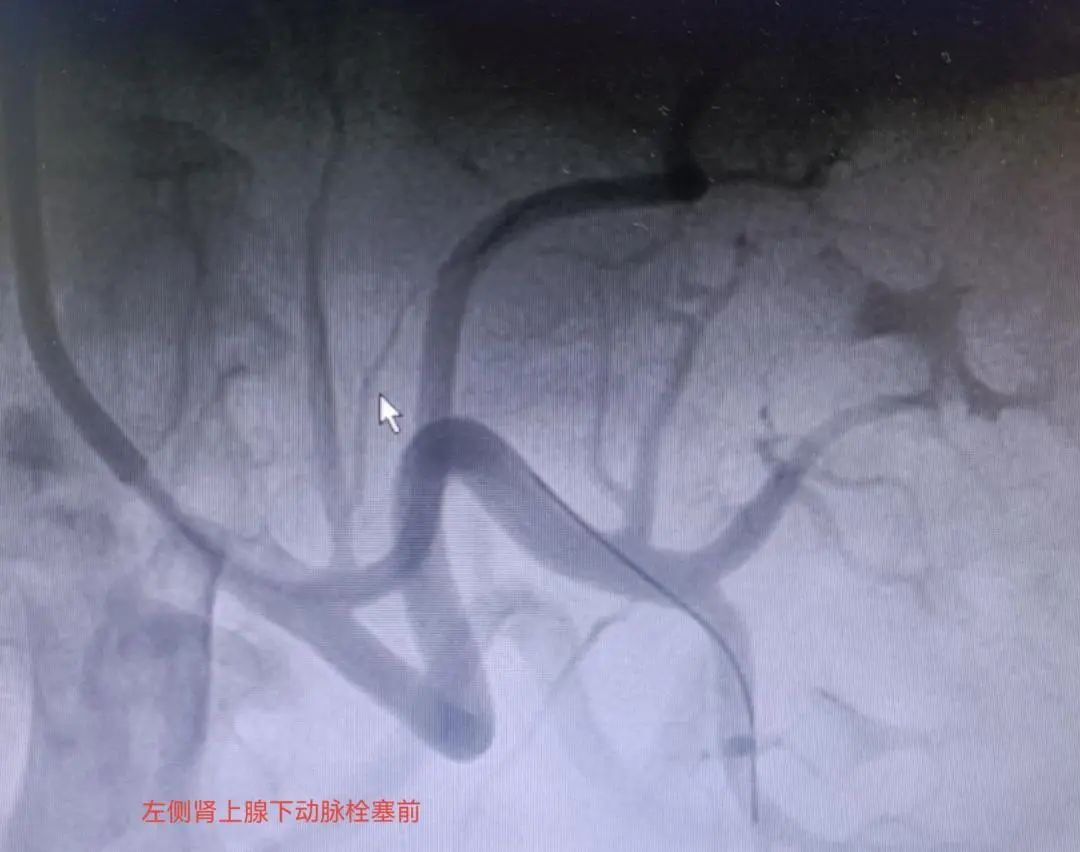

针对患者病情,由绵阳市三医院心血管内科主任蔡国才带领的介入团队仔细分析论证,经反复推敲后确定为患者行经皮超选择性肾上腺动脉栓塞术。该术是在患者清醒状态下进行局麻穿刺,通过毁坏相应肾上腺,减少醛固酮分泌的方式,达到治疗高血压的目的。

超选择性肾上腺动脉栓塞术是一种微创性手术,通过利用栓塞剂选择性栓塞供应病变的肾上腺动脉,让病变肾上腺部分坏死,从而抑制醛固酮的产生,是治疗原发性醛固酮增多症的一种有效方法。

该手术由日本学者Hokotate在1997年首次应用,较传统治疗,利用这项技术治疗原发性醛固酮增多症且有手术时间短、创伤小、出血少、术后恢复快的独特优势,部分患者可达到根治高血压的目的,为高血压治疗开辟了新的途径。(胥红娟、曹东亮)